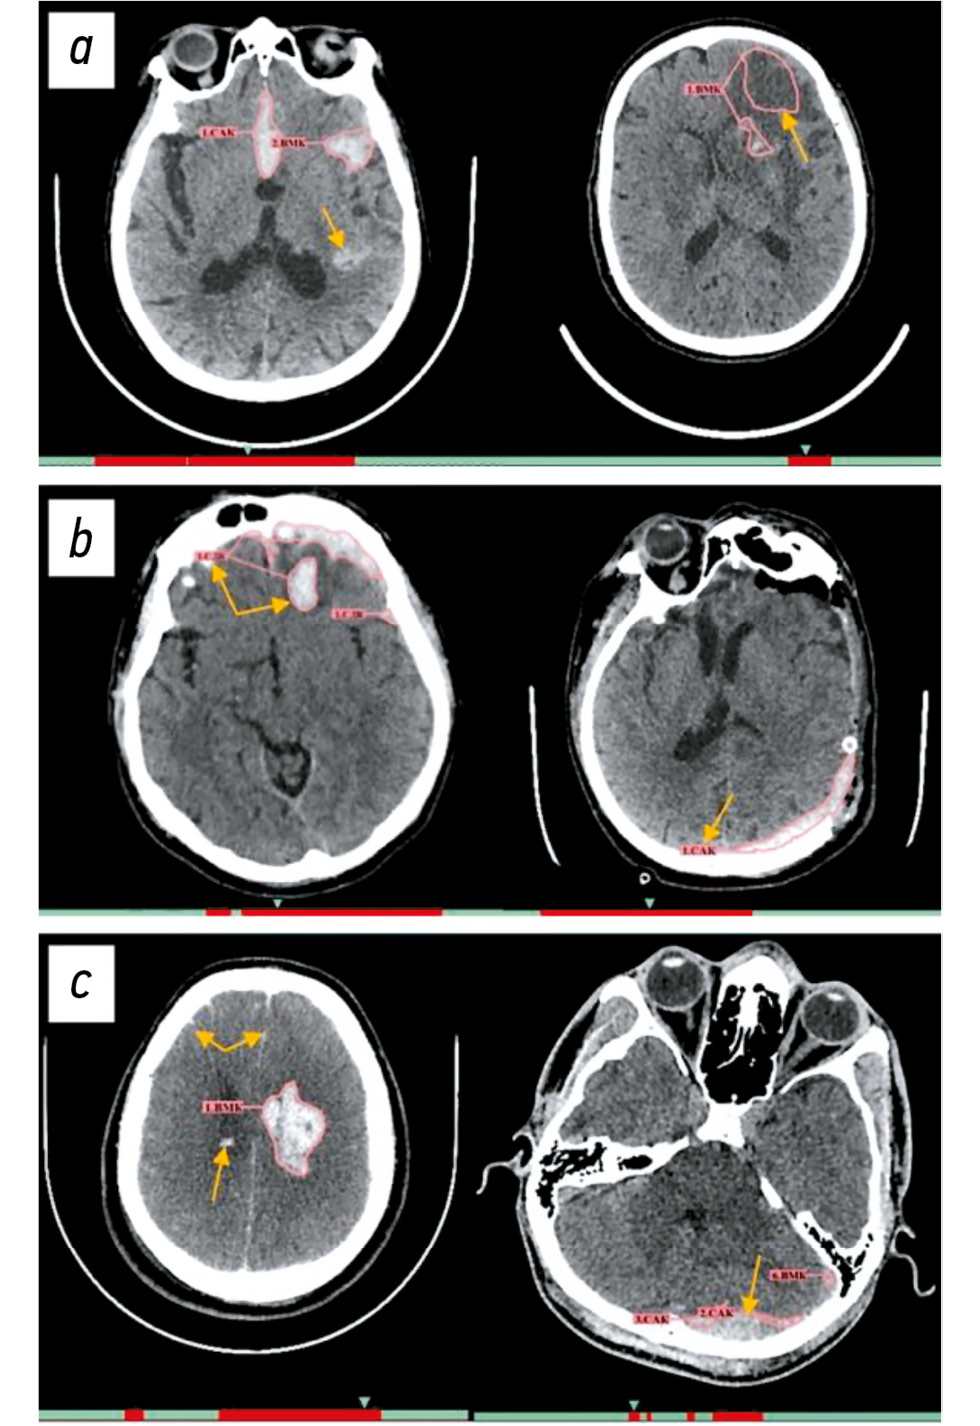

Одним из наиболее частых примеров частично корректного срабатывания можно назвать случаи, когда при множественных кровоизлияниях ИИ-сервис выделял один тип кровоизлияния, но пропускал другой. Так, на рис. 4, a слева пропущено внутримозговое кровоизлияние в левом полушарии, а на рис. 4, c слева ИИ-сервис корректно его сегментировал в левом полушарии, но не отметил внутрижелудочковое кровоизлияние в правом полушарии, а также межполушарное субарахноидальное кровоизлияние и по бороздам в обоих полушариях. Также частым случаем некорректных срабатываний является частичная сегментация кровоизлияния с ошибочным определением его типа (см. рис. 4, c) — справа представлено субдуральное кровоизлияние, которое ИИ-сервис идентифицировал как субарахноидальное. Гораздо реже среди примеров частично корректного срабатывания можно отметить полностью корректную сегментацию патологической зоны кровоизлияния, но неверное определение его/их типа (см. рис. 4, b) — справа внутримозговое кровоизлияние ошибочно классифицировано как субдуральное, а слева субдуральное кровоизлияние отнесено к субарахноидальному.

Рис. 4. Примеры частично корректных срабатываний сервиса искусственного интеллекта: a — корректное определение типа кровоизлияния и некорректная их сегментация; b — корректная сегментация областей кровоизлияния, ошибочное определение их типа; c — частичное выделение одних кровоизлияний и пропуск других, некорректные как сегментация, так и определение типа.

Всего отмечено 152 ложноположительных результата. Наиболее частыми их причинами являлись сегментации магистральных артерий, венозных синусов и частично кальцифицированных оболочек мозга (рис. 5, a).

Рис. 5. Примеры ложно-положительных (a) и ложноотрицательных (b) срабатываний сервиса искусственного интеллекта.

ИИ-сервис не выявил патологические изменения на 14 изображениях КТ ГМ. Наиболее часто встречали ложноотрицательные результаты при субарахноидальных кровоизлияниях — 8 случаев (см. рис. 5, b, в центре и справа). Реже наблюдали пропуски внутрижелудочковых кровоизлияний — 2 случая (см. рис. 5, b, слева), внутримозговых кровоизлияний — 2 случая, а также по одному случаю субдурального и эпидурального кровоизлияния.